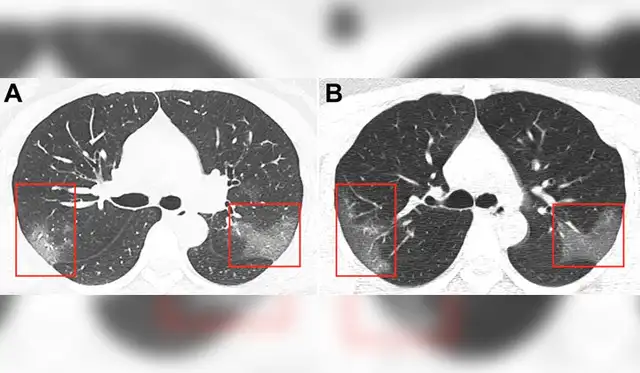

Evolución de las manchas en los pulmones después de tres días. Imagen: First Hospital of Lanzhou University.

En la primera radiografía, los médicos detectaron unas manchas blancas en la esquina inferior de los pulmones de la paciente, que se mantiene en el anonimato. Los expertos comparan la tonalidad de las manchas con la “opacidad de vidrio esmerilado”.

Sin embargo, las manchas se extendían hasta los bordes de los pulmones de la mujer, lo que antes también se había detectado en los infectados por coronavirus como el SARS y MERS.

Luego de tres días de tratamiento, los médicos realizaron nuevas radiografías para descartar un caso de neumonía común. Al ver las imágenes, se percataron de que las manchas blancas eran más notorias y extensas.